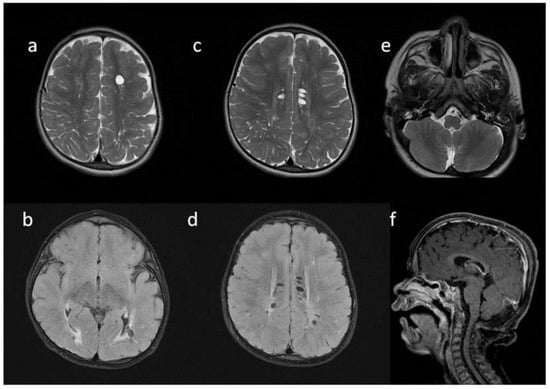

| Patient No | 1 | 2 | 3 | 4 | 5 | |

|---|---|---|---|---|---|---|

| age at exam | 4 mo | 3 yo | 1 y 2 mo | 1 y 11 mo | 3 y 2 mo | 14 yo |

| radiological imaging | ||||||

| WM signal abnormalities | + | + | + | |||

| areas of delayed myelination | + | + | + | + | + | |

| enlarged perivascular spaces | + | + | + | + | ||

| narrow corpus callosum | + | +/− | + | + | ||

| prominent ventricular system | +/− | + | +/− | + | + | |

| arachnoid cyst | + | + | ||||

| optic nerve sheath enlargement | + | + | ||||

| J-shaped sella turcica | + | + | + | +/− | + | +/− |

| craniocervical junction distortion | + | +/− | + | + | ||

| posterior fossa horns | + | + | + | + | ||

| fluid effusion temporal bone | + | + | + | + | +/− | |

| closed sagittal suture | + | + | + | |||

| vertebral bodies deformity | + | + | ||||

| intervertebral disc anomalies | + | + | ||||